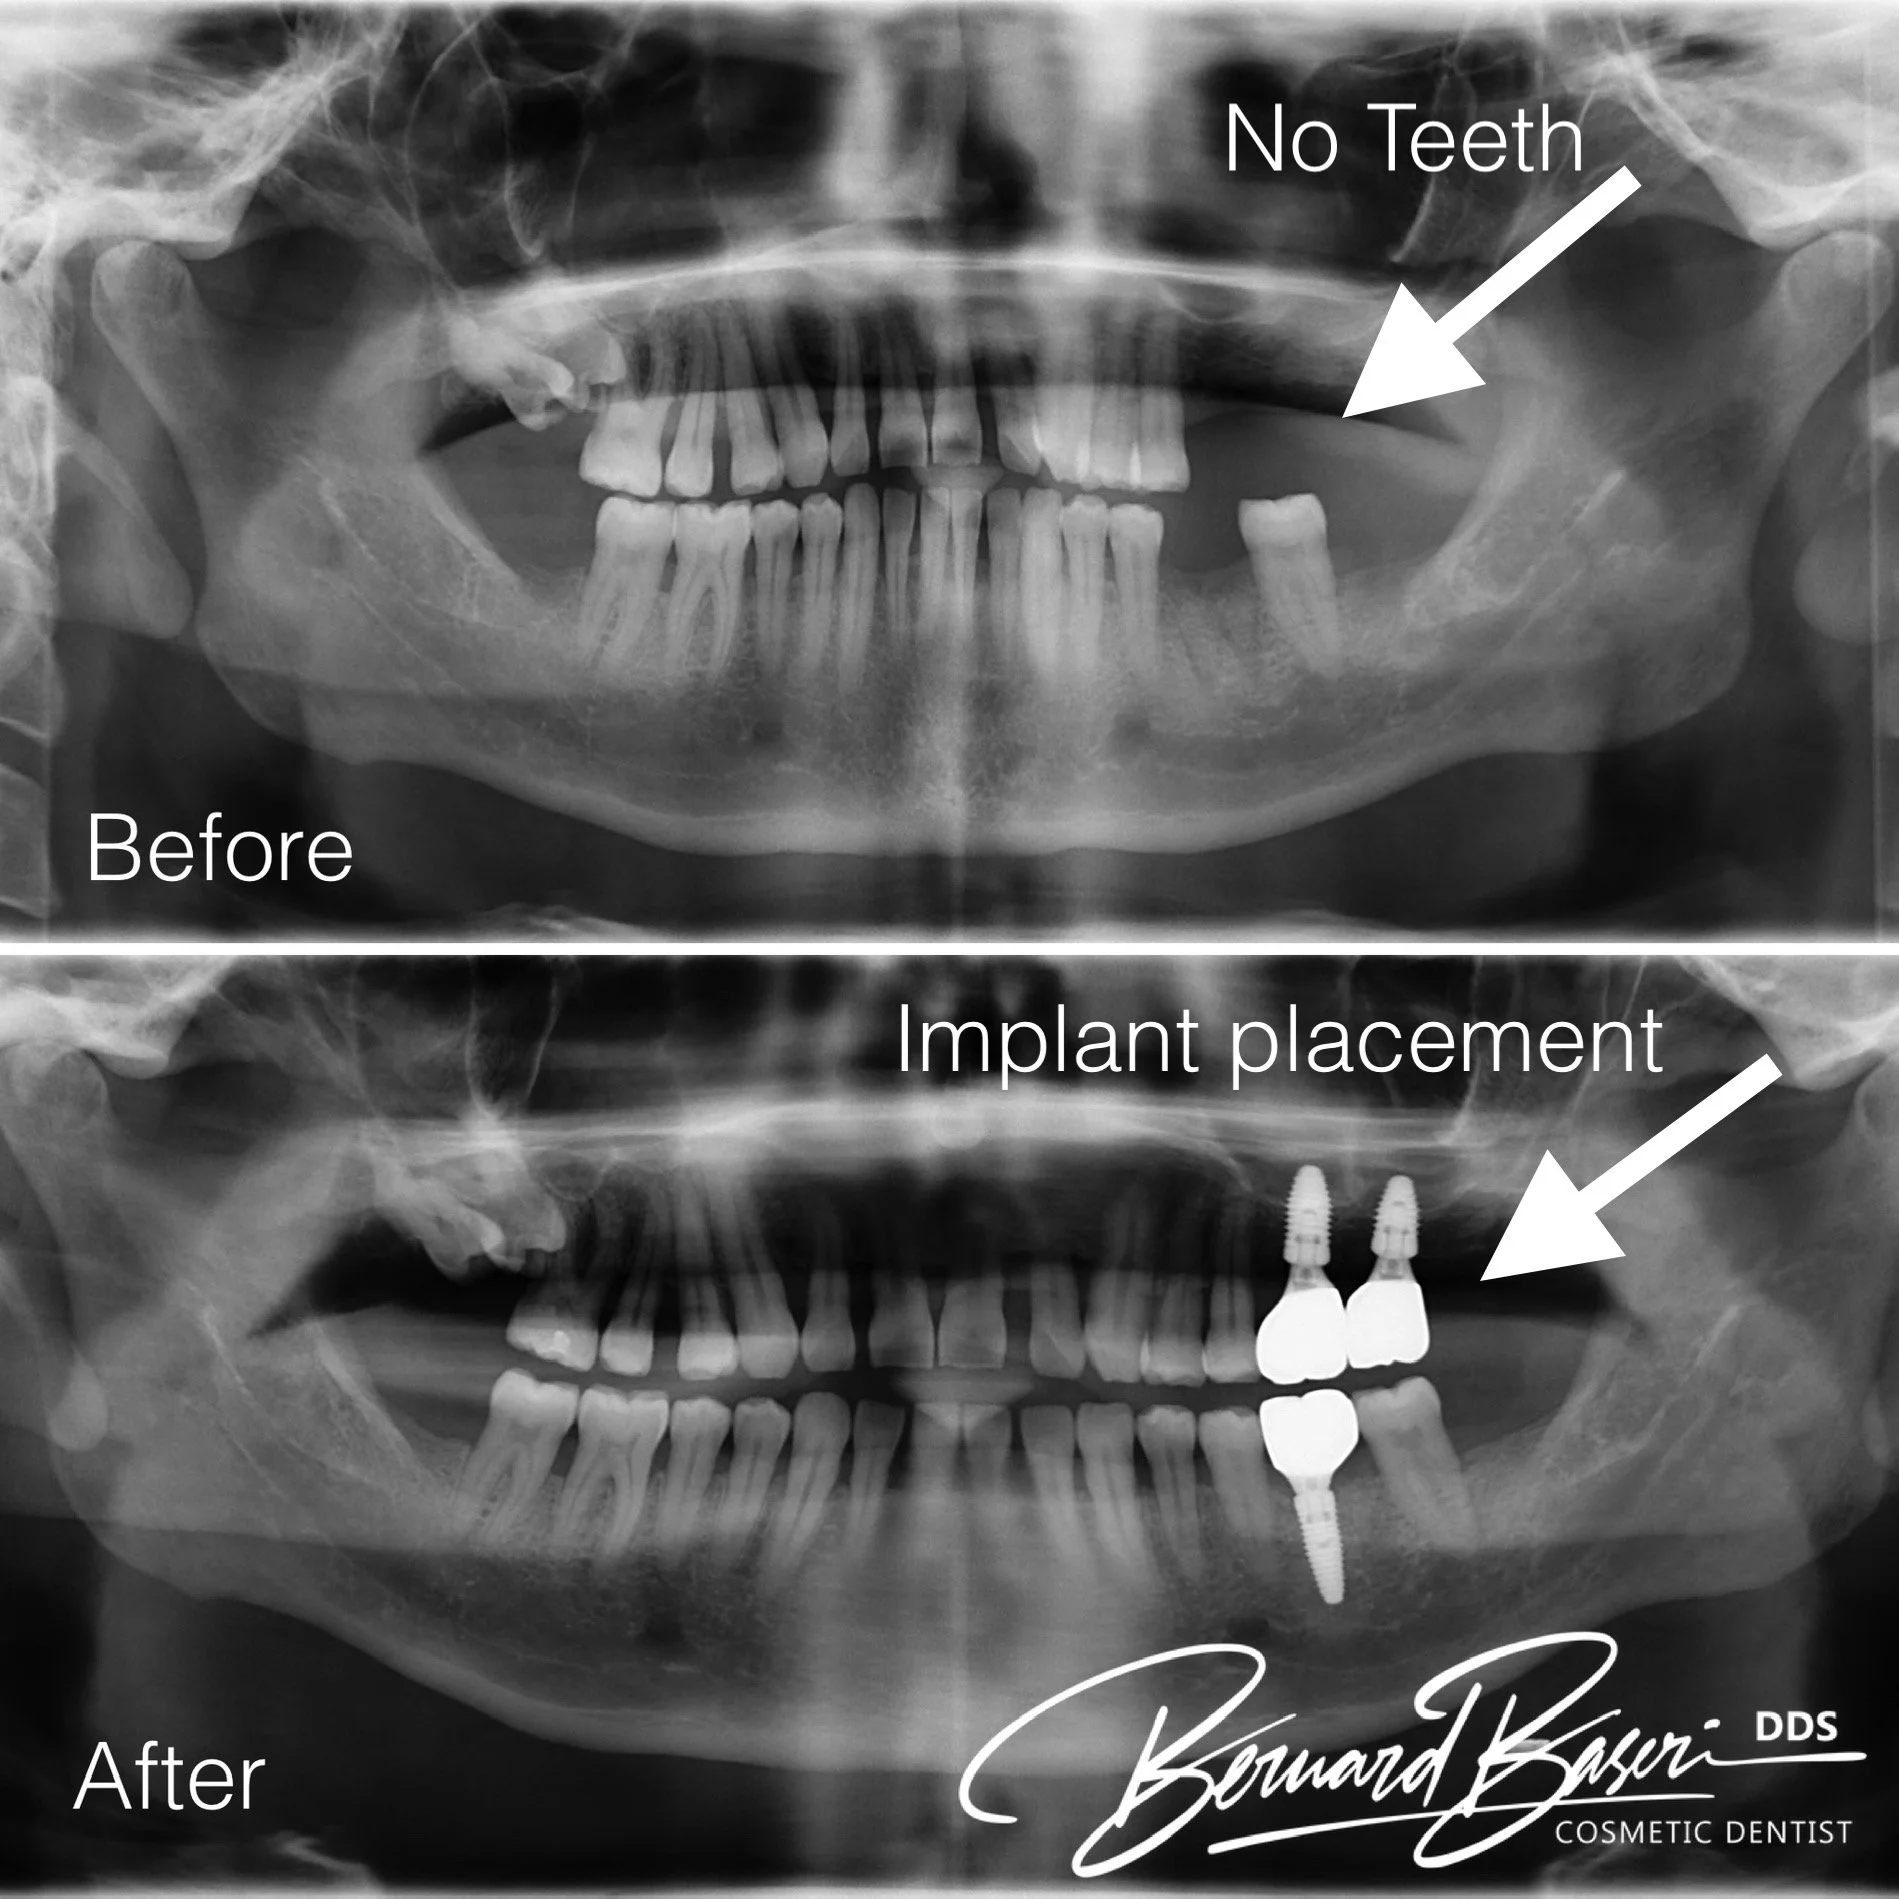

Dental Implant Xray Dental Implant Problems And Solutions We offer tips on how to best protect your investment, and go over signs there may be problems in the months and years after dental implant surgery. Placing dental implants involves several critical steps, each. From minor complications to more serious issues, common dental implant problems can occur, leaving patients in search of solutions to restore their oral health and. Dental Implant Problems And Solutions.